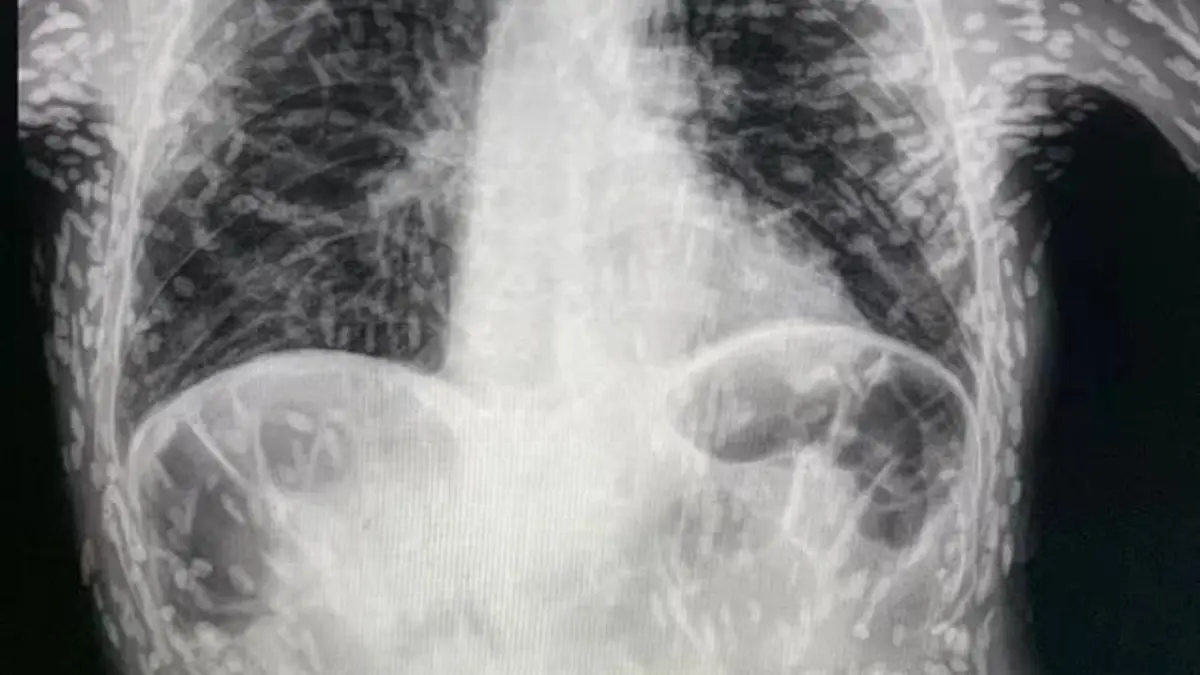

Das veröffentlichte Röntgenbild zeigt Hunderte von hellen Flecken, die jeweils die verkalkten Überreste des Bandwurms darstellen. Die so genannte Zystizerkose tritt auf, wenn die Larven des Schweinebandwurms in Gewebe wie Muskeln oder Gehirn eindringen. Dort bilden sie harte, knötchenartige Zysten, die sich wie Klumpen unter der Haut anfühlen können. Doch wie gefährlich ist das?

Und weiter: „Wenn wir die Eier aufnehmen, dann entwickeln sich - wie das in diesem Fall auch war - Larven im Darm. Eine Vorform davon kann sich an die Innenwand des Darms anheften, dadurch in die Blutgefäße und darüber im Prinzip in jedes Organ gelangen. So kann es passieren, dass irgendwann der ganze Körper durchsetzt ist von lauter Larven.“ In Fall des Patienten in Brasilien sei wohl hauptsächlich die Lunge befallen gewesen. „Das äußert sich dann zum Beispiel in Form von Atemproblemen“, so der Mediziner. Oder eben durch Husten.

Bilden die Larven Zysten in den Organen, spricht man von einer Zystizerkose. Sind die Läsionen verkalkt, wie es bei dem Patienten in Brasilien der Fall war, sei eine Behandlung nicht zwangsläufig nötig. Sie seine zwar unangenehm, aber im Allgemeinen harmlos, da die Larven nicht überleben,

Um eine Zystizerkose nachzuweisen, sei ein „bildgebendes Verfahren wie Röntgen oder ein MRT“ nötig. Positiv ist jedoch, dass Menschen mit Zystizerkose die Eier nicht auf andere Menschen übertragen können – im Gegensatz zu den Patienten mit einer aktiven Bandwurminfektion.